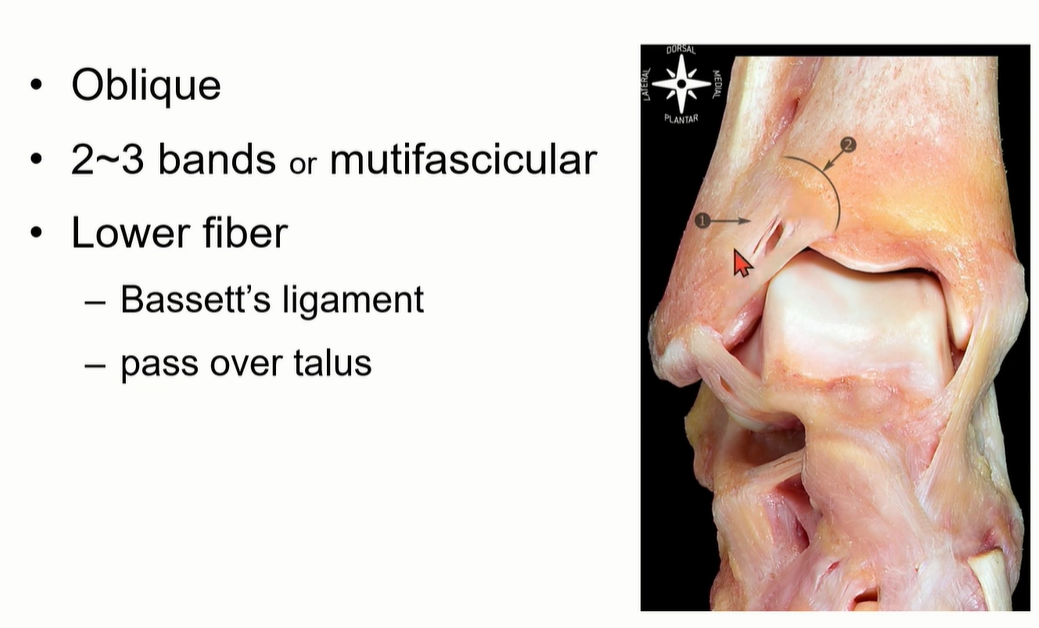

4-2. ATTFL

Tibia plafond의 anterolateral tubercle에서 시작해서 distal fibula에 붙고, 비스듬하게 여러 가닥으로 구성되어 있다.

AITFL의 가장 inferior bundle은 main bundle에서 떨어져 있는데, 이 fiber를 Bassett's ligament 라고 부른다. Talus와 impinge를 일으키기도 하는데, anterolateral ankle impingement를 뜻함.

MRI에서는 coronal cut에서 AITFL 를 관찰하기 용이하다. Multi-fascicular 구조이기 떄문에, Tear로 오인하면 안됨.

특히 Axial cut에서는 일부 cut에서 discontinuity 가 관찰될 수 있는데, oblique한 주행 방향으로 인한 정상 소견일 수 있다는 것을 염두해야 한다.